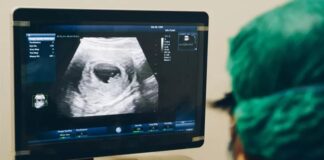

Bu bir ilk; Bebek doğmadan ana rahminde tedavi edildi

Kanadalı tıp uzmanları, dünyada nadir görülen ve ölümcül olarak bilinen genetik hastalığı olan bir bebeği, ana...